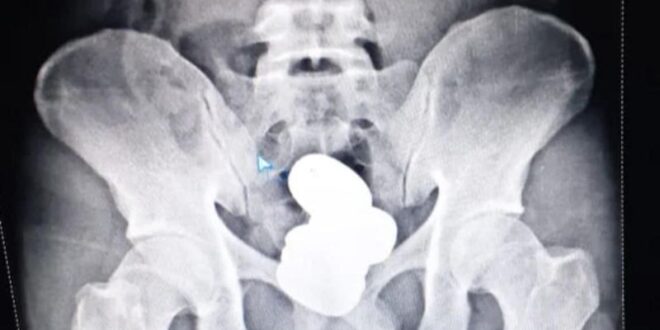

Las autoridades le hicieron una radiografía que reveló la presencia de cuatro cápsulas en el recto que contenían en total más de 900 gramos de pasta de oro, por un valor aproximado de 56 mil 664 dólares, según el comunicado de las fuerzas de seguridad.